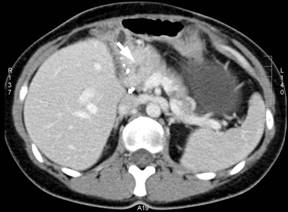

On the following abdominal CT scans performed between 90 and 95 months of follow-up, gradual enlargement of the pancreatic head with the suspicion of a tumor was noted (Figure 4). This was confirmed by both endoscopic ultrasound (Figure 5) and 11C-acetate PET/CT scan (Figure 6). Moreover, microscopic examination of the fine-needle aspirate of the pancreatic head tumor obtained during endoscopic ultrasound showed the presence of atypical hepatocytes within the tumor. In view of this, the patient was accepted for surgical treatment again and pancreaticoduodenectomy with the �uncut Roux� reconstruction was successfully performed at 97 months since the initial surgery. The pathologic examination revealed the diagnosis of a metastatic fibrolamellar hepatocellular carcinoma of the head of the pancreas. The postoperative course was uneventful and the patient did not experience recurrence within the last 18 months after pancreaticoduodenectomy. Following five laparotomies and one thoracotomy for fibrolamellar hepatocellular carcinoma and its recurrences, the patients remains well at the overall follow-up of 114 months at present.

Figure 4. Enlargement of the head of the pancreas (arrow) revealed by abdominal CT scan at 95 months of follow-up. |